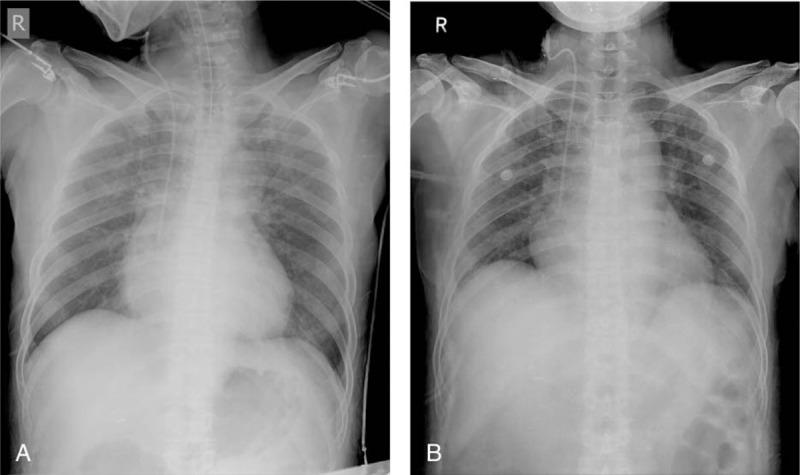

A 57-year-old woman with no significant medical history underwent spinal anesthesia for arthroscopic meniscus resection after rupturing the right knee meniscus. Preoperative electrocardiogram revealed sinus bradycardia (54 beats/min) and a left anterior fascicular block. Spinal anesthesia was performed with 11 mg of 0.5% heavy bupivacaine, and the upper level of sensory loss was at T6. Dexmedetomidine infusion was planned at a loading dose of 1.0 mcg kg min over 10 minutes, followed by 0.7 mcg kg min intravenously, as a sedative. Two minutes after dexmedetomidine injection, her heart rate decreased to 31 beats/min and asystole was observed within 10 seconds.

一名57岁无重大病史的女性,因右膝半月板破裂接受关节镜半月板切除术的脊髓麻醉。术前心电图显示窦性心动过缓(54次/分钟)和左前分支阻滞。采用11毫克0.5%重比重布比卡因进行脊髓麻醉,感觉丧失的上界在T6。计划以1.0微克/千克/分钟的负荷剂量静脉输注右美托咪定10分钟,随后以0.7微克/千克/分钟静脉输注作为镇静剂。右美托咪定注射两分钟后,她的心率降至31次/分钟,并在10秒内出现心脏停搏。